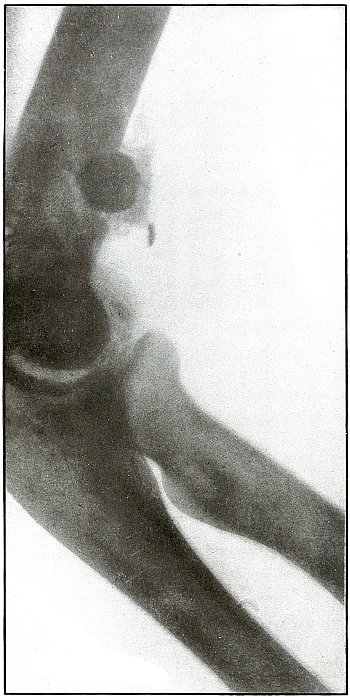

Gunshot fracture, elbow |

48 |